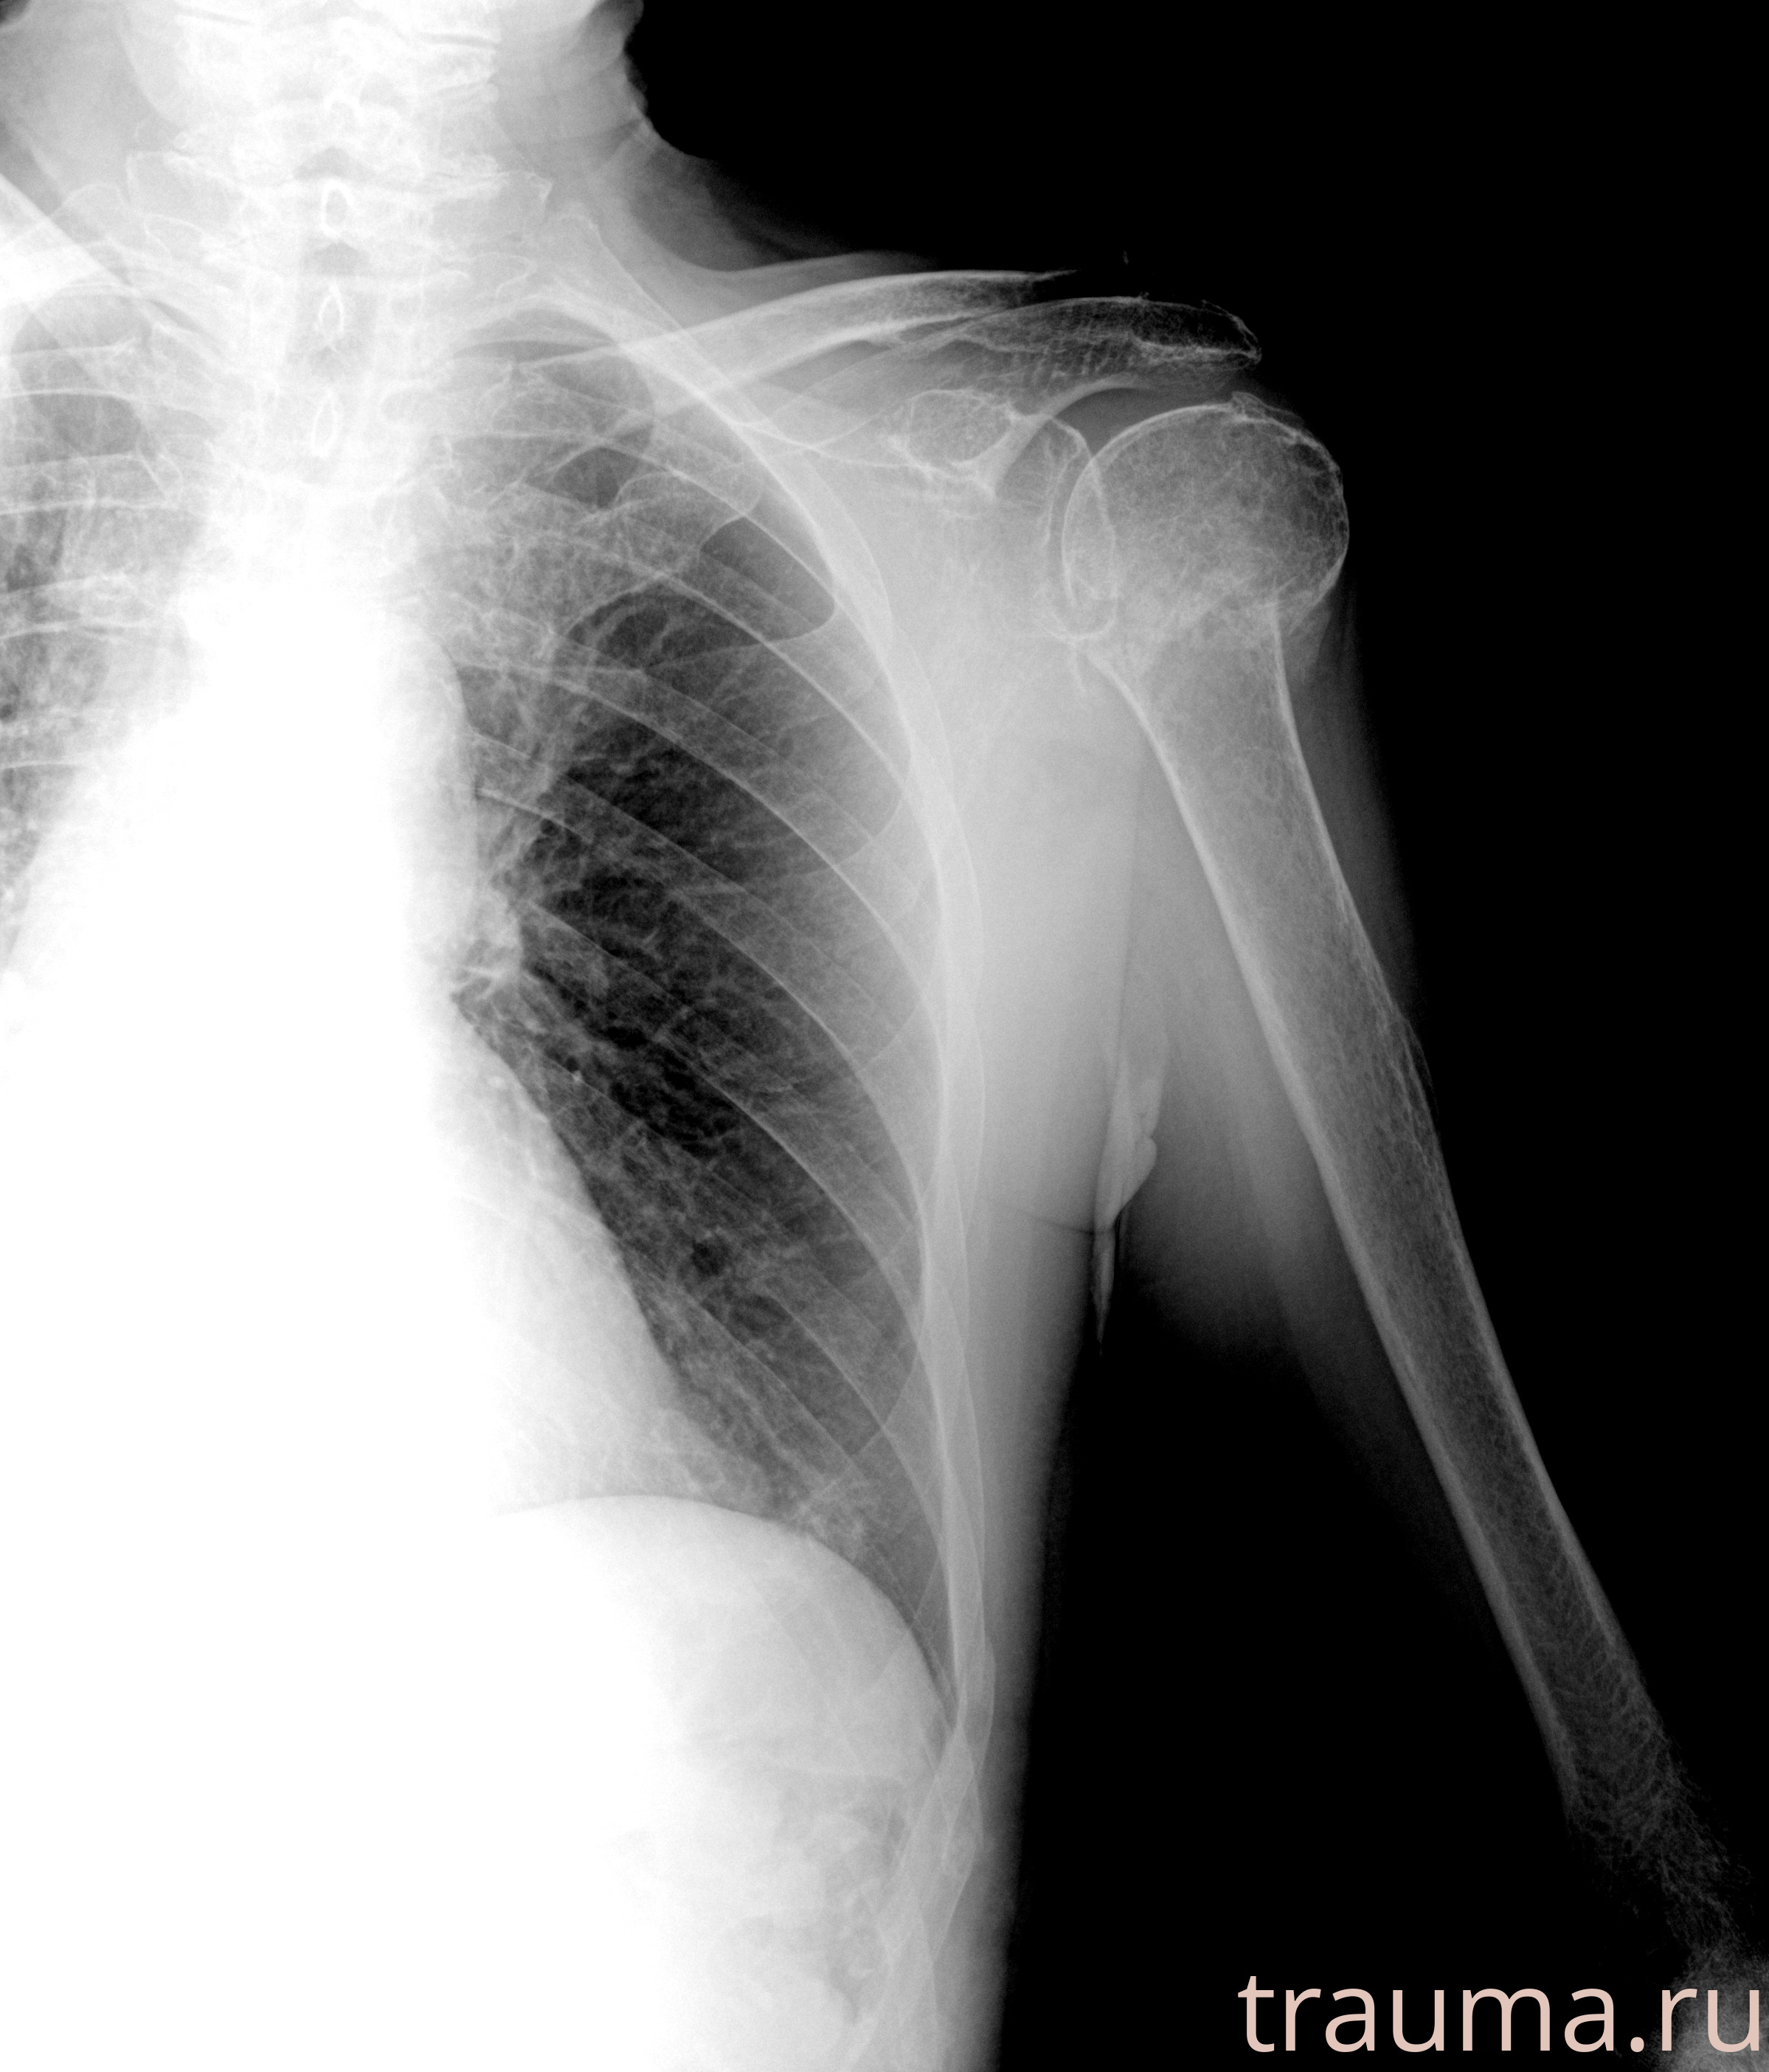

Рентгенограммы

Рентген на дому: по вашему адресу приезжает врач-рентгенолог, травматолог-ортопед с мобильным рентгеновским аппаратом, проводит диагностику травмы или заболевания, делает необходимые рентгенограммы, дает рекомендации по дальнейшему лечению. Получить качественные снимки в домашних условиях возможно благодаря уникальной методике, разработанной МосРентген Центром для института  Склифосовского

при переломе шейки бедра и пневмонии от компании МосРентген Центр - партнера Института имени Склифосовского